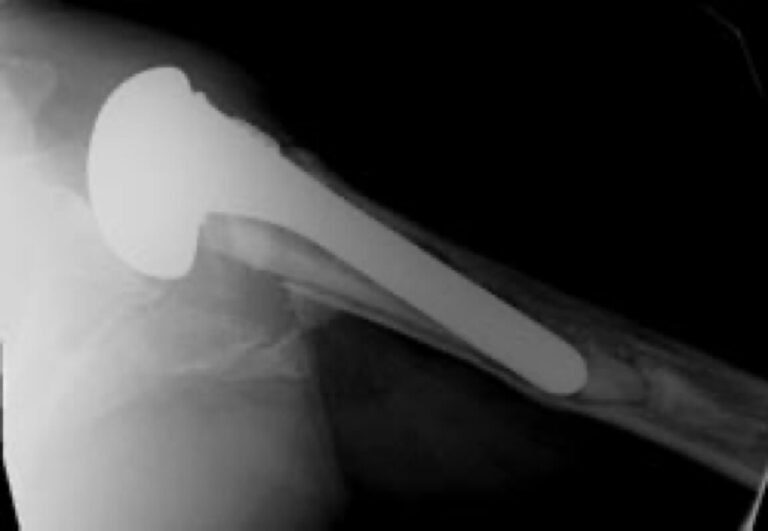

American Shoulder and Elbow Surgeons > Stryker/Wright/Tornier, Solar

Stryker/Wright/Tornier, Solar